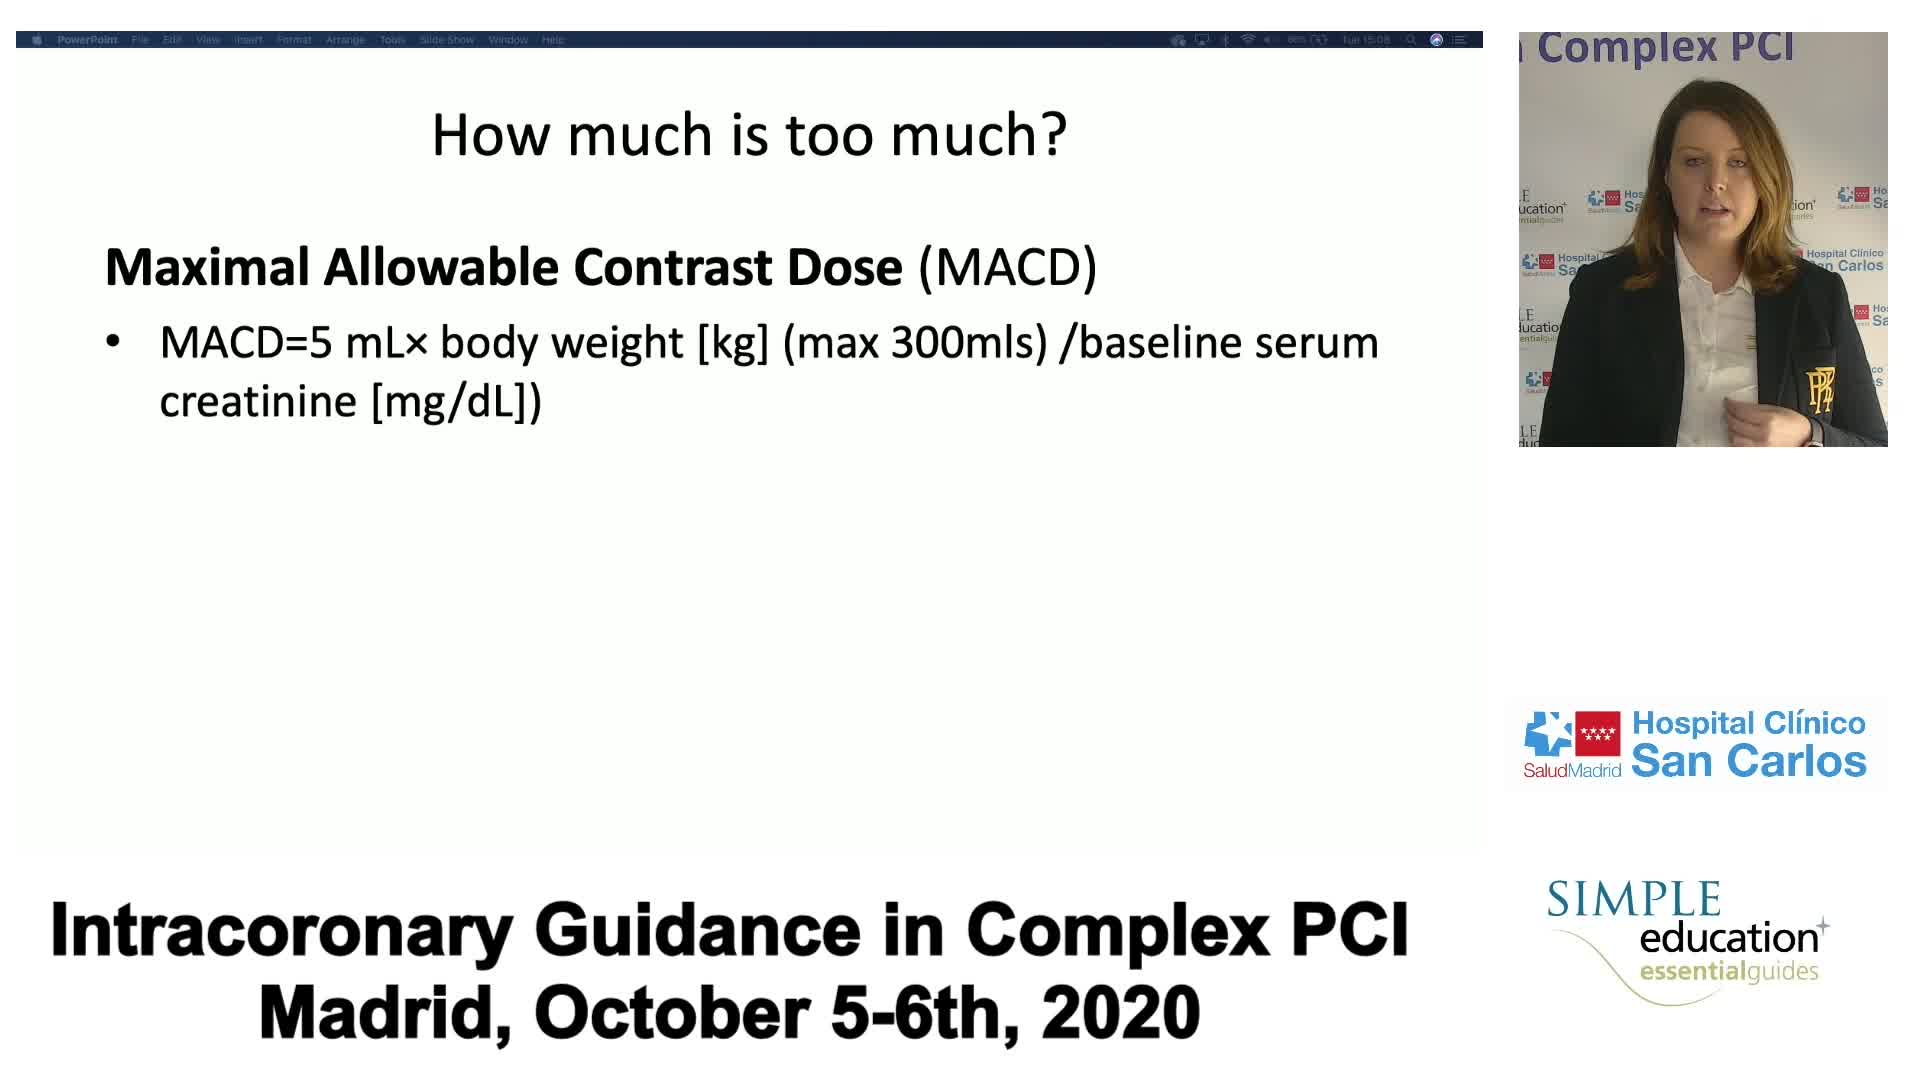

Prevention of Contrast Induced Nephropathy: Fact, Fiction and Fantasy - Christopher Baker